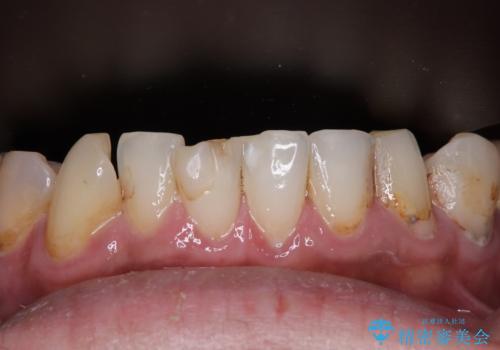

- すぐに欠けてしまう前歯や、むし歯で全顎的に処置された歯を気にして来院された患者様です。

元来むし歯が多く、さらに受け口傾向の咬み合わせを気にしていらっしゃいました。

当初はむし歯処置が必要な歯のみの治療予定でしたが、捻転や咬み合わせを可及的に改善したいとのことで、全顎的にオールセラミッククラウンにて補綴治療を行うこととしました。